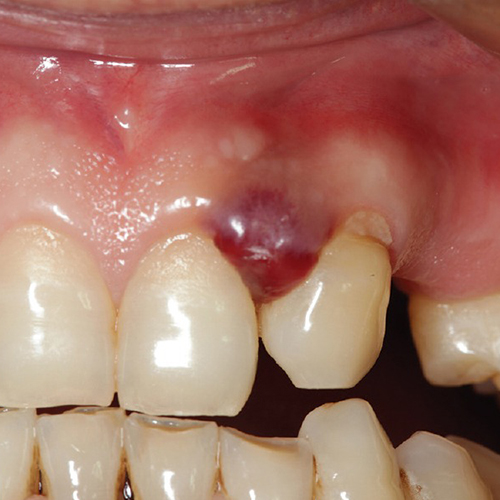

۱) پیوژنیک گرانولوما: یک ضایعه برجسته روی لثه است ( البته گاهی روی زبان و سایر مخاط هم دیده میشود) با کوچکترین دستکاری خونریزی میکند و اندازه آن شاید به چندین سانتی متر هم برسد. دلیل بروز آن شاید جرم زیر لثه باشد و شاید تغییرات هورمونی در زنان به ویژه در ایام بارداری.

تصاویری از تومورهای دهانی